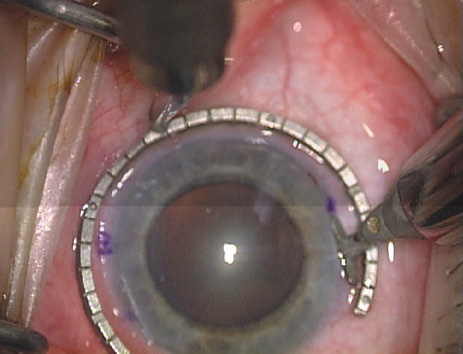

Case 1 is a 68-year-old male who presented for right cataract surgery. His refraction was −1.00 +2.25 × 80 and was recorded as reliable, consistent with his modest cataract density. Keratometry readings were 44.75 × 75 and 43.00 × 165. Corneal topography confirmed slightly more than 2.00 D of regular and slightly oblique cylinder. Consulting the nomogram, a plan was devised for a pair of LRIs to be centered over the 75-degree axis, with each incision delineating 45 degrees of arc. A single plane phaco incision was used and maintained at a size of less than 3.2 mm (Figs. 811).

Fig. 8. Steep meridian is confirmed intraoperatively by keratoscopy. In this left eye viewed from the temporal side, the “short axis” of the corneal mire is seen to be at the 75-degree meridian. (Reprinted from Hardten DR, Lindstrom RL, Davis EA. Phakic Intraocular Lenses: Principles and Practice. Thorofare, NJ: SLACK Incorporated, 2004, with permission.)

Fig. 9. The broad hash marks of the fixation ring/gauge are centered over the 75-degree meridian, using the 6:00 limbal mark for orientation. Alternatively, a Mendez gauge may be used. (Reprinted from Hardten DR, Lindstrom RL, Davis EA. Phakic Intraocular Lenses: Principles and Practice. Thorofare, NJ: SLACK Incorporated, 2004, with permission.)